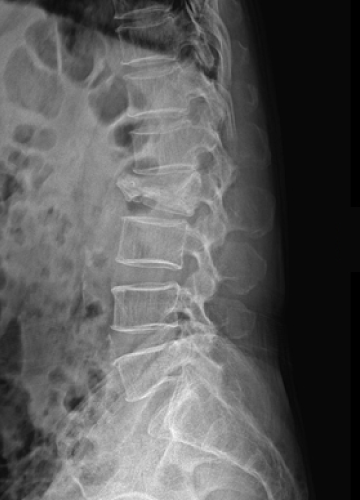

척추 고정술 치료 방법

2020.06.09

2020.08.11

ㆍ환자 동의를 받은 자료이며, 이미지 사진은 실물과 다를 수 있습니다.

ㆍ모든 자료는 새움병원 자료입니다.